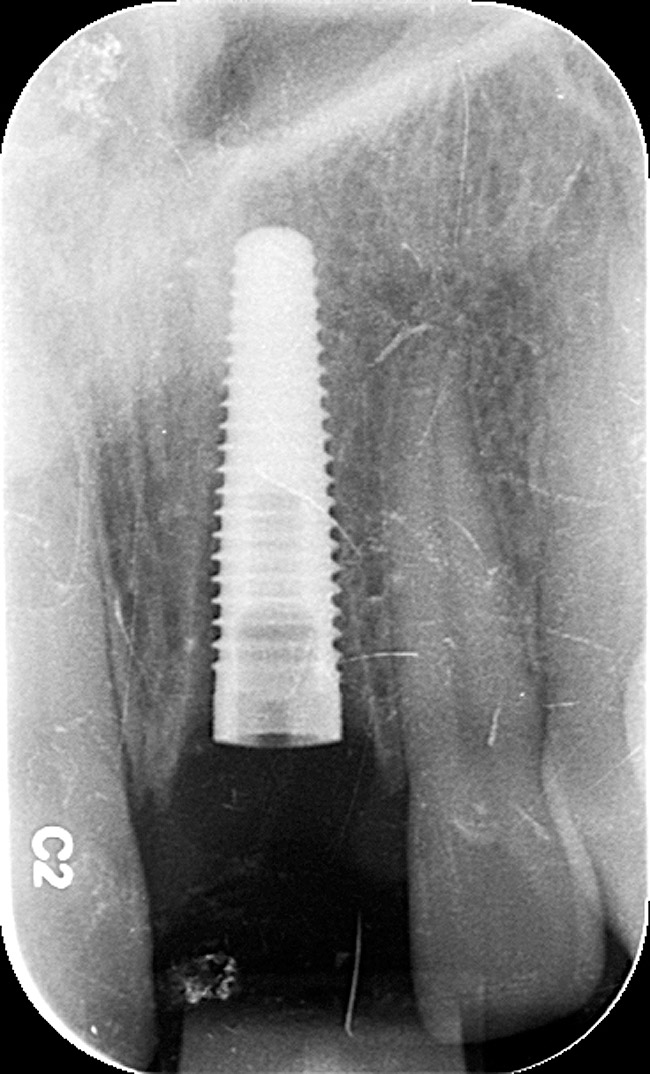

Figure 20  Screw-retained zirconia crown, customized zirconia stock abutment (one-piece restoration), site No. 9—final periapical view.

Figure 20

The restorative dentist preferred a screw-retained one-piece final restoration to facilitate retrievability, if ever necessary. The laboratory technician customized a zirconia stock abutment, applying multiple layers of a specialized porcelain whose coefficient of thermal expansion matched that of the zirconia abutment. A soft-tissue cast was created from the impression supplied by the restorative dentist. Additional layers of specialized zirconia porcelain were applied to develop the proper crown contour and emergence profile.

The final screw-retained crown was delivered and torqued onto the implant to 35 Ncm; the restorative dentist then sealed the screw access with a cotton pellet and composite (Figure 20 and Figure 21). Various views of the final crown are shown in Figure 22 through Figure 25, including a full-face photograph.